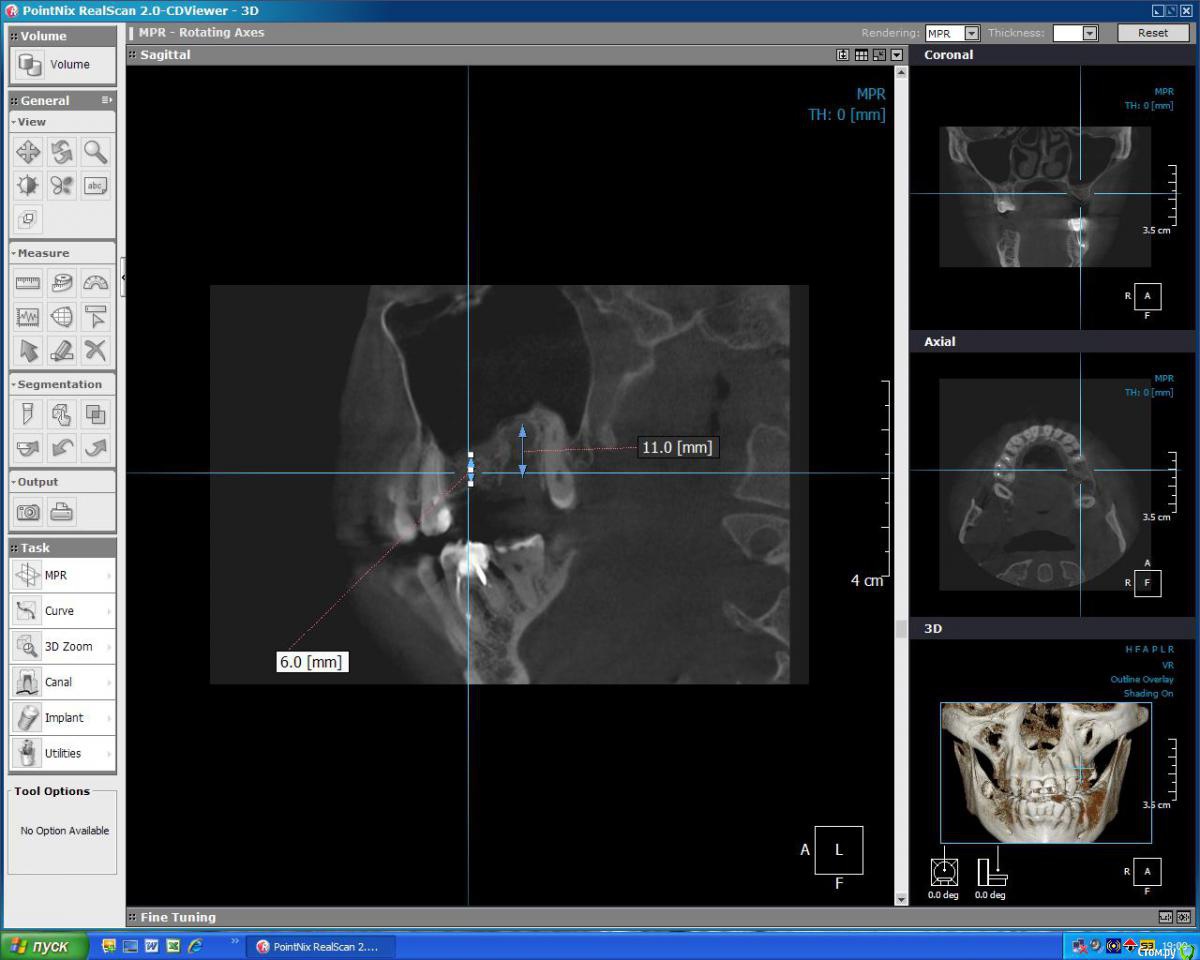

kuznetsovaev Опубликовано 19 октября, 2015 Поделиться Опубликовано 19 октября, 2015 (изменено) Добрый вечер, уважаемые врачи, подскажите мне пожалуйста какой вариант имплантации более правильный. Буду очень надеяться на вашу помощь. Так же буду рада если будут еще какие-то может более верные варианты. Заранее благодарю. Были кисты на верхней и нижней челюсти, в связи с чем удалили зубы.КТ от 10.10.2015г. Мне 33, пол женский.Верх лево: 7зуб и киста над ним удалены 18.09.2015, соседний 6-ой удален 3года назад.Низ право: 6-ой зуб удален 20.04.2015, киста и 7-8 зубы удалены 13.08.2015г. Пока хожу по клиникам ищу "своего" врача и слышу разные мнения. Вариант 1.1. Нижние 6 и 7 импланты ставить без костной пластики через пару месяцев (в декабре), кость сама нарастет. Сделать прицельный снимок перед имплантацией и все, т.к. очертания кости уже видны, кость просто станет более плотной, а границы уже не изменятся.2. Верхние 6 и 7 ставить через полгода после синуслифтинга. Вариант 2.1. Нижний 6 без костн.пластики, а в 7 лунку пересадить свой костный материал закрепив минигвоздиками (если правильно запомнила). Спустя три месяца ставить импланты сразу в 6 и 7.2. Верх синуслифтинг над 6 и 7кой, через полгода ставить и 6 и 7 имплантат. В этом варианте прозвучала еще мембрана и 4 болтика, я не поняла куда ее крепить будут. Вариант 3.1. Низ 6 готова к имплантации, а в 7ку засыпать микс кости моей и инородной. Спустя два-три месяца ставить импланты сразу в 6 и 7.2. А на верхней челюсти над 6-ой подъем пазухи, а над 7-кой не надо поднимать, а нужно засыпать в ее лунку смесь моей и инородной кости, закрыть мембраной. Ну и через полгода имплантация. Вариант 4.1. Внизу без костной пластики.2. Верх через закрытый синус досыпят кости с одновременной имплантацией. Изменено 19 октября, 2015 пользователем kuznetsovaev Ссылка на комментарий

red_butler Опубликовано 21 октября, 2015 Поделиться Опубликовано 21 октября, 2015 Спасибо вам большое за ваш план лечения! Я не могла понять когда и что делать в какой последовательности, и то я коронки уже собралась ставить на 1.5 (еще не подготовили корни) и 1.6 (уже готов был, под коронку готовили, ждали когда я 1.5 смогу перелечить) вот в этом месте - одновременный синуслифтинг с имплантацией я правильно поняла?Возможно и без синуслифта получится, если нет то одновременно. 1 Ссылка на комментарий

faity Опубликовано 21 октября, 2015 Поделиться Опубликовано 21 октября, 2015 да одновременно, ну или как коллега предлагает без синуса, просто короткие импланты, Strauman в этом году линейку 4мм имплантов запустил, Astra Tech 6мм. правда на жевательные зубы я бы их не ставил 1 Ссылка на комментарий